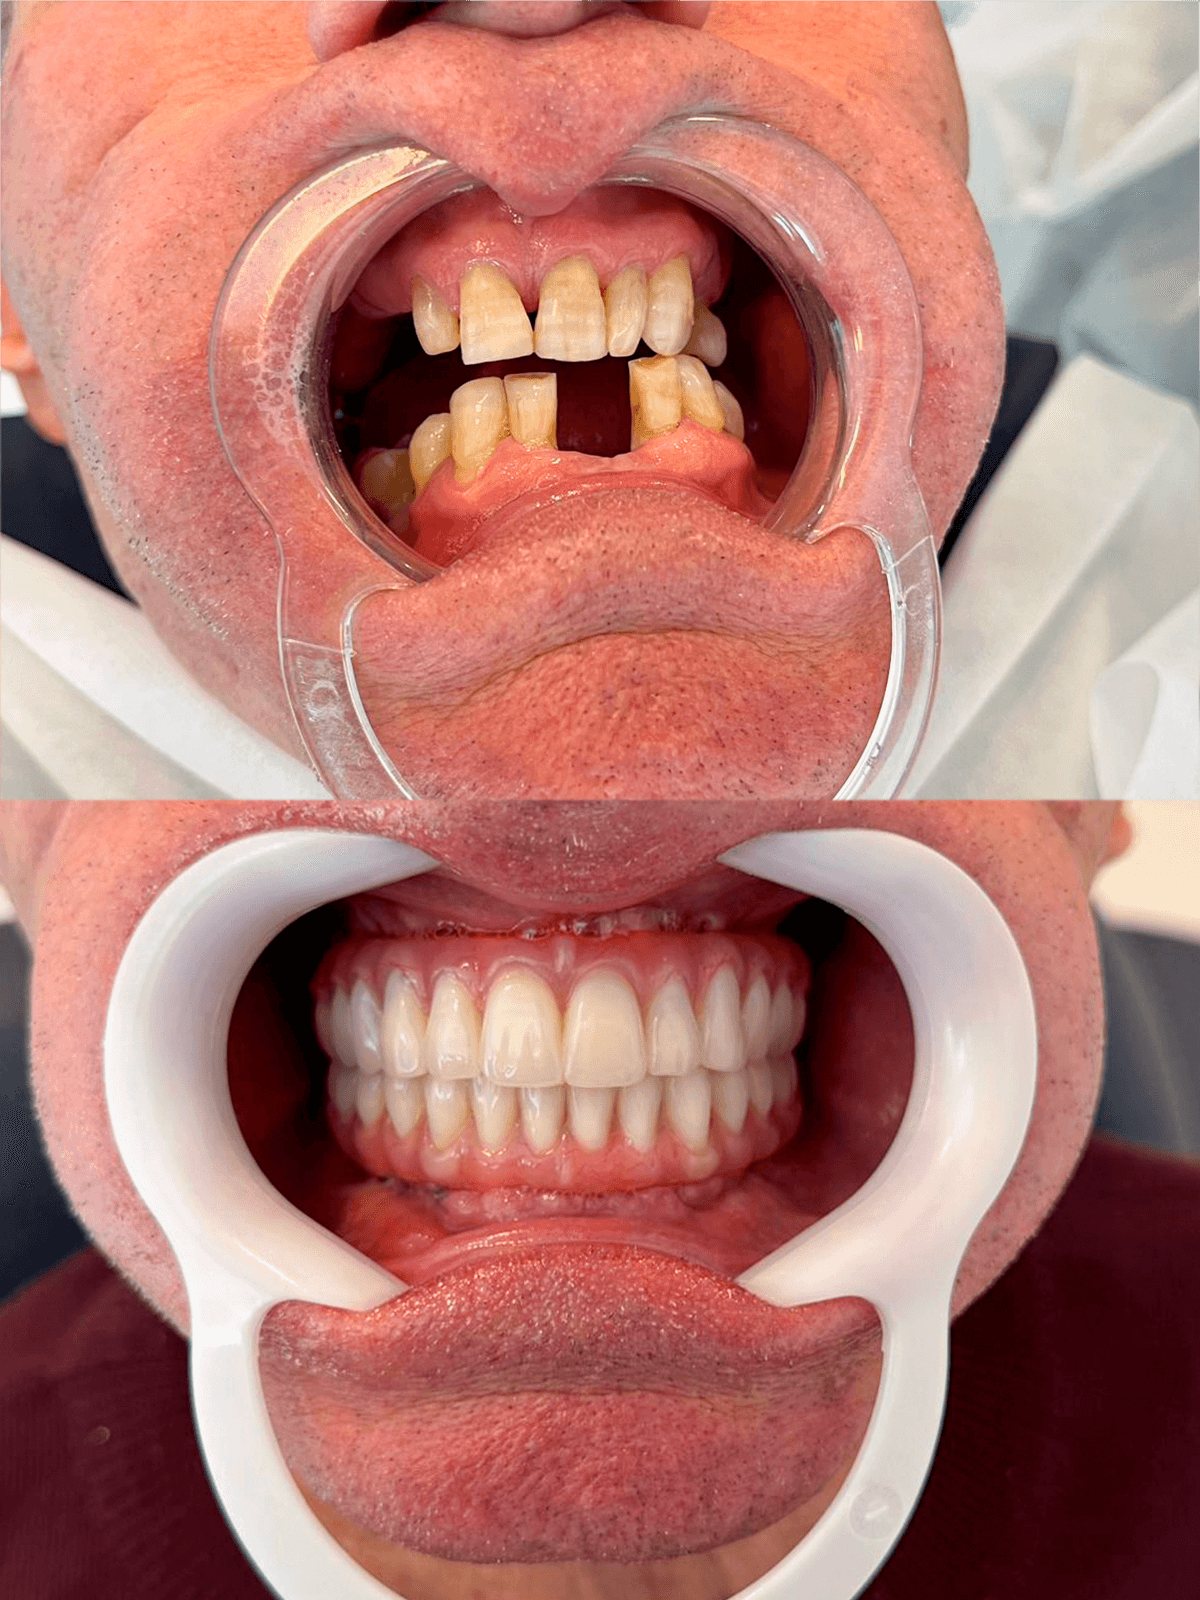

Próteses dentais

O caminho para um sorriso completo e confiante, restaurando sua estética e funcionalidade.

Implante Dentário

A solução permanente e natural para recuperar seus dentes perdidos e sorrir sem preocupações.